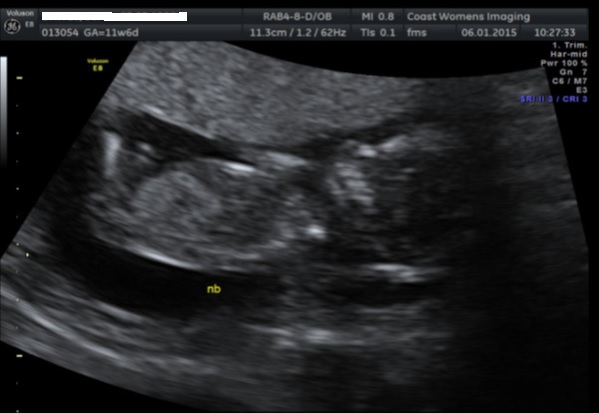

Just wondering if anyone has a guess on my scan pics, the technician made me feel stupid when I asked her about the nub theory and if she was familiar with it, so I didn't ask for a clear shot. I cant make anything out..